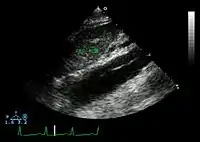

Ultrasound

The transesophageal echocardiogram (TEE) is a good test in the diagnosis of aortic dissection, with a sensitivity up to 98% and a specificity up to 97%. It has become the preferred imaging modality for suspected aortic dissection. It is a relatively noninvasive test, requiring the individual to swallow the echocardiography probe. It is especially good in the evaluation of AI in the setting of ascending aortic dissection, and to determine whether the ostia (origins) of the coronary arteries are involved. While many institutions give sedation during transesophageal echocardiography for added patient comfort, it can be performed in cooperative individuals without the use of sedation. Disadvantages of TEE include the inability to visualize the distal ascending aorta (the beginning of the aortic arch), and the descending abdominal aorta that lies below the stomach. A TEE may be technically difficult to perform in individuals with esophageal strictures or varices.